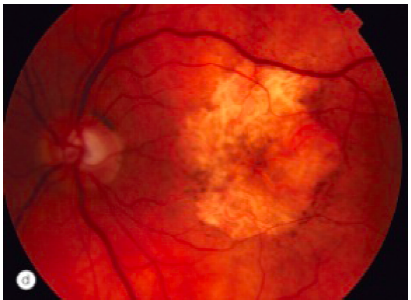

Neovascular “wet” AMD

MECHANISM OF VISION LOSS?

Mechanism of vision loss

Clinical Presentation of Neovascular AMD?

Vision? Visual field defect? (3)